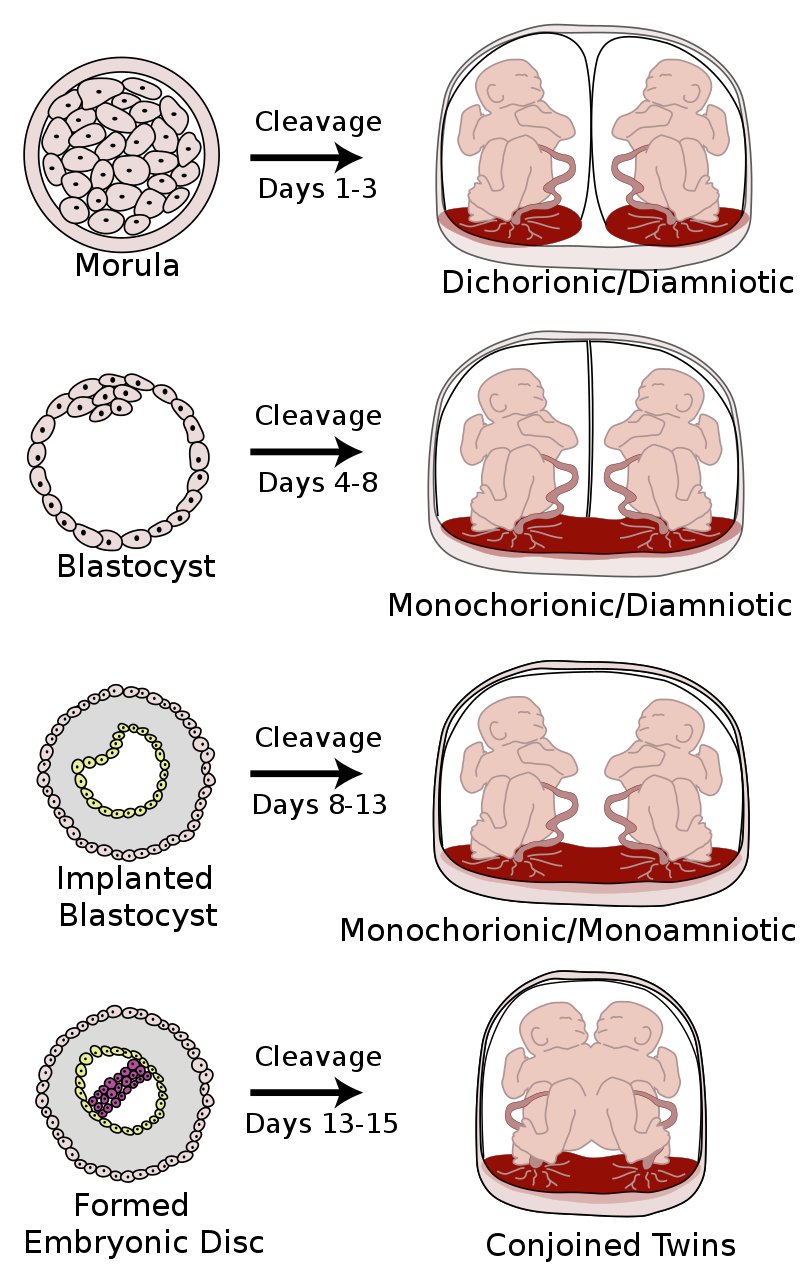

一般来说,可以延迟出生的双胞胎,有2个胎盘,2个羊膜囊,所以一个胎儿出生后,并不会影响其他胎儿继续发育。